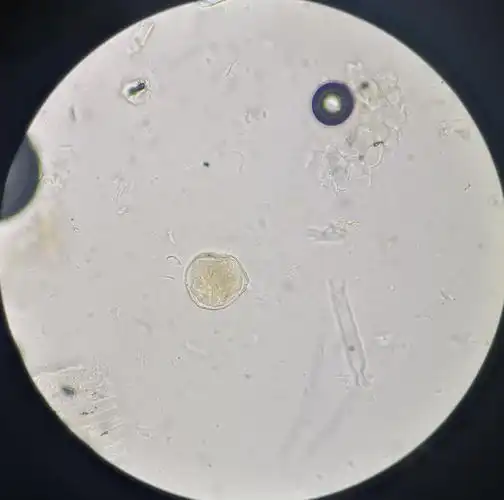

18药剂六班药植显微实验作业小组成员:陈燕婷13 窦琳薇19

拍的显微镜下的蒲黄(花粉粒)

18级药剂七班实验小组成员,王展鸿,陈雅善

18级药剂七班显微镜实验小组:毛惠婷,吴东梓